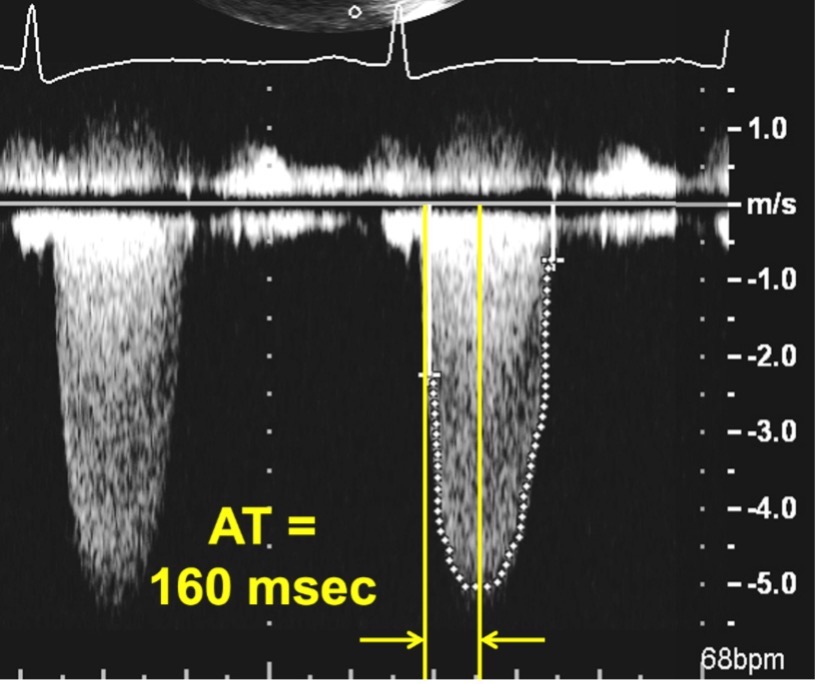

Progressive stenosis will lead to a prolonged acceleration time (AT), which is the time to the peak of the jet velocity as a result of delayed peaking of the velocity during systole. Therefore, the Doppler profile contour of an aortic prosthesis with stenosis with thrombi or pannus formation will be blunted and rounded as opposed to the triangular shape characteristic of a normally functioning prothesis (Figs. 4,5). This can be quantified by the ratio of the AT to the total ejection time (ET) over which blood flow occurs during systole, as a normal AT/ET ratio is less than 0.32. The AT as well as the AT/ET can also help distinguish true prosthetic obstruction from other conditions that confer a “functional” obstruction such due to high flow states (which can result from anemia, thyrotoxicosis, AV fistulas, or significant aortic regurgitation), pressure recovery, or patient prosthesis mismatch that can also lead to an elevated mean aortic prosthetic gradient. A functional obstruction will present with a peak velocity greater than 3 m/s, but the AT will be less than 80 ms, and the AT/ET, though it may be mildly elevated will not typically be greater than 0.37 [50, 51].

Fig. 5.Continuous Wave Doppler of an aortic prosthesis with structurally obstructive hemodynamics. Note the rounded contour of the Doppler jet, with an acceleration time (AT) of 160 msec.